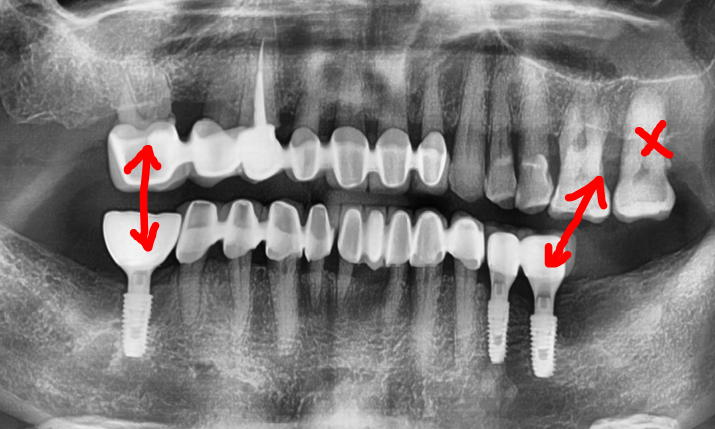

엑스레이를 보면, 아래턱에 어금니들이

결손이 되어있는 것을 볼 수 있습니다.

여튼 위, 엑스레이를 보면서 하나씩 설명드릴게요

1) 이분은, 구강 내 전체적으로 치주염을 앓고

계셨으며 치석 또한 곳곳에 많이 쌓여있었습니다.

따라서, 치조골이 많이 위축 됨에 따라서 하방으로

이동되어 치아의 뿌리가 겉으로 다 드러나

있는 것을 볼 수 있습니다.

다만, 브릿지 보철로 연결이 되어있기 때문에

치아 정출에 관련되어서는 크게 신경 쓸 것은

아니나 추후에는 치료를 반드시 꼭 해야 되는 상황.

2) 1번내용과는 다르게,

상악 어금니만 남아있으며

아래에는 어금니들이 없습니다.

즉, 교합관계를

형성하지 않고 있기 때문에

교합 기능을 전혀 이룰 수 없는 상태입니다.

아울러, 윗니들은 아랫니들이 없기 때문에

점차 아래로 내려오는 ‘치아 정출’ 현상이

지속적으로 나타나면서 추후에 쉽게 발치로

이어지게 되는 상황이 우려됩니다.

사진을 기준으로, 좌측의 경우에는

지르코니아 크라운이 연결되면서

대합치의 정출을 막을 수 있는 위치에

배치가 되었으나

우측의 경우에는 맨 끝에 있는 후방치는

그렇지 않은것을 볼 수 있습니다.